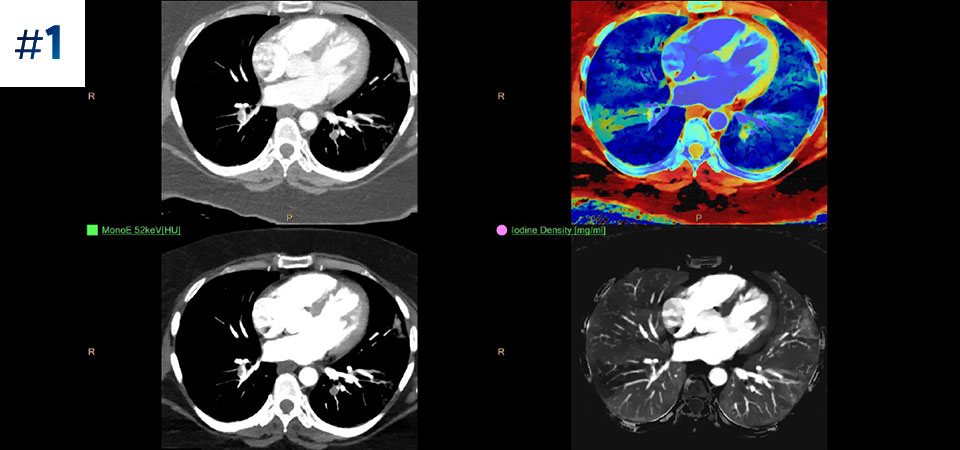

Scanează ca de obicei O singură scanare pentru date convenţionale şi spectrale obţinute rapid, cu doză redusă, pentru fiecare pacient, de fiecare dată.

Are întotdeauna disponibilă componenta spectrală Rezultate 100% spectrale, pentru toate scanările care sunt întotdeauna disponibile la cerere, chiar și retrospectiv.

Reduce numărul de examinări ulterioare O mai bună caracterizare și vizualizare a țesuturilor poate reduce nevoia de scanare ulterioară pentru examene suboptime și descoperiri accidentale.